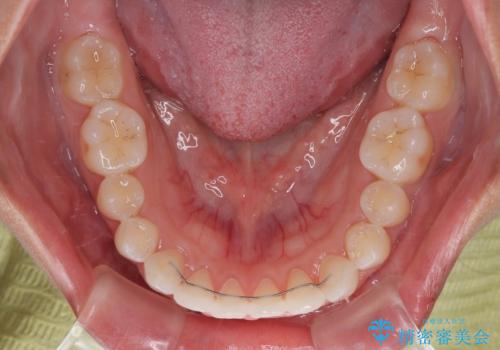

僅か半年強、あっという間に治療を終えることができました。

- 矯正治療後の保定が不十分だと後戻り(元の位置に戻ろうとする動き)をします